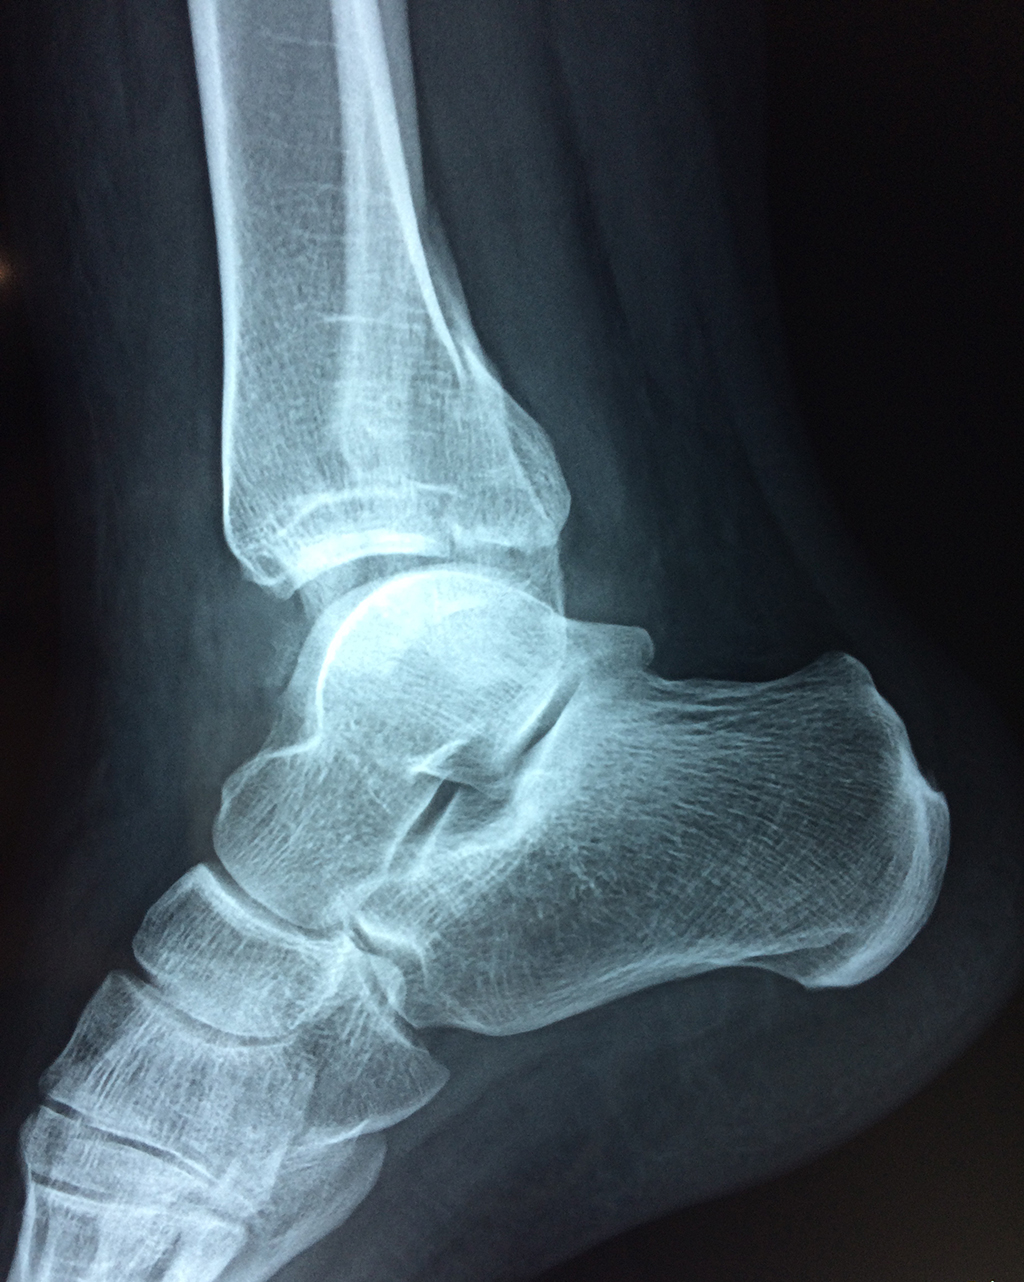

Cirugía de Tibia y Peroné

Una fractura de tobillo es la rotura de uno o más de los huesos del tobillo. Estas fracturas pueden ser:

- Parciales (el hueso está sólo parcialmente fisurado, no del todo).

- Completas (el hueso está perforado y está en 2 partes).

- Producirse en uno o ambos lados del tobillo.

Algunas fracturas de tobillo pueden requerir cirugía si:

- Los extremos de los huesos están desalineados entre sí (desplazados).

- La fractura se extiende hasta la articulación del tobillo (fractura intra-articular).

- Los tendones o ligamentos (tejidos que sujetan los músculos y los huesos entre sí) están rotos.

- El médico cree que sus huesos probablemente no sanen apropiadamente sin cirugía.

- El médico considera que la cirugía puede permitirle una recuperación más rápida y confiable.

- En los niños, la fractura involucra la parte del hueso del tobillo donde el hueso está creciendo.

Cuando se necesita cirugía, es probable que esta implique el uso de clavijas de metal, tornillos o placas para sostener los huesos en su lugar mientras la fractura se consolida. Los elementos de soporte pueden ser temporales o permanentes.